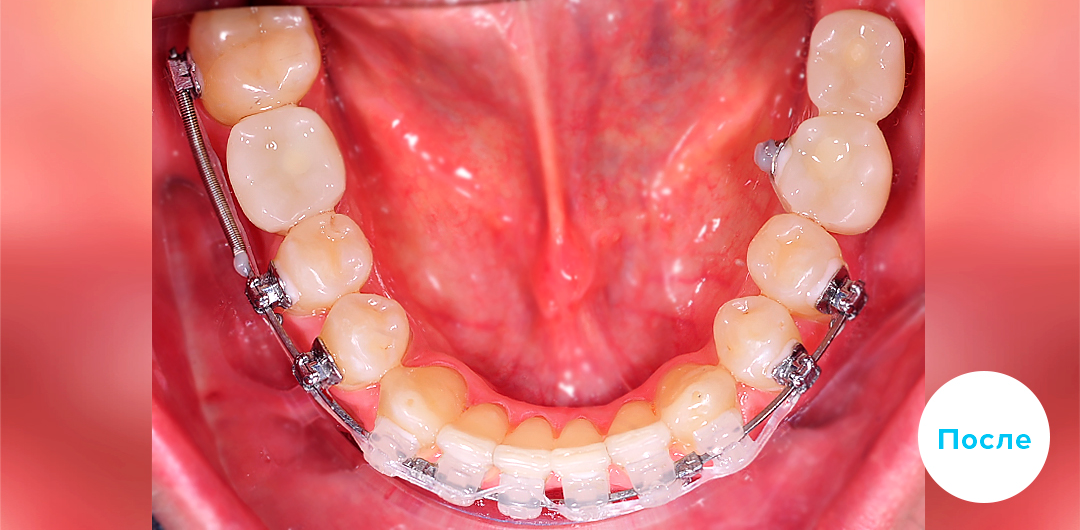

Результаты лечения